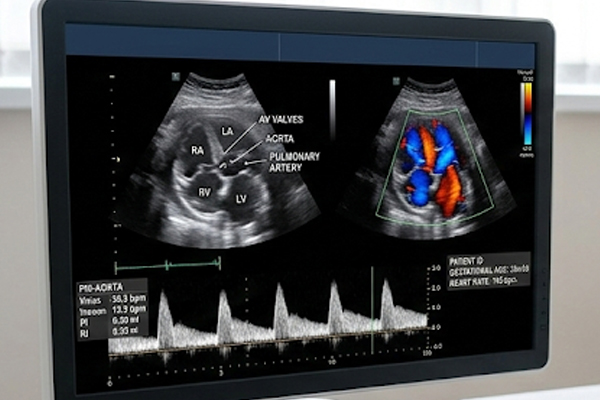

É um exame relacionado ao estudo anatômico e funcional do coração do feto utilizando-se o ultrassom. Estuda-se o tamanho e a estrutura do coração (câmaras, válvulas e vasos principais), e os fluxos sanguíneos.

Estudo direcionado para investigação de mal formações cardíacas, cardiopatias congênitas, das cavidades cardíacas, dimensões, análise das funções ventriculares, estudo das valvas cardíacas, análise dos fluxos sanguíneos intra cardíacos, análise dos vasos da base (aorta e tronco da artéria pulmonar) e pericárdio e outras condições inerentes à circulação fetal. Avaliação do ritmo e de arritmias cardíacas fetais.